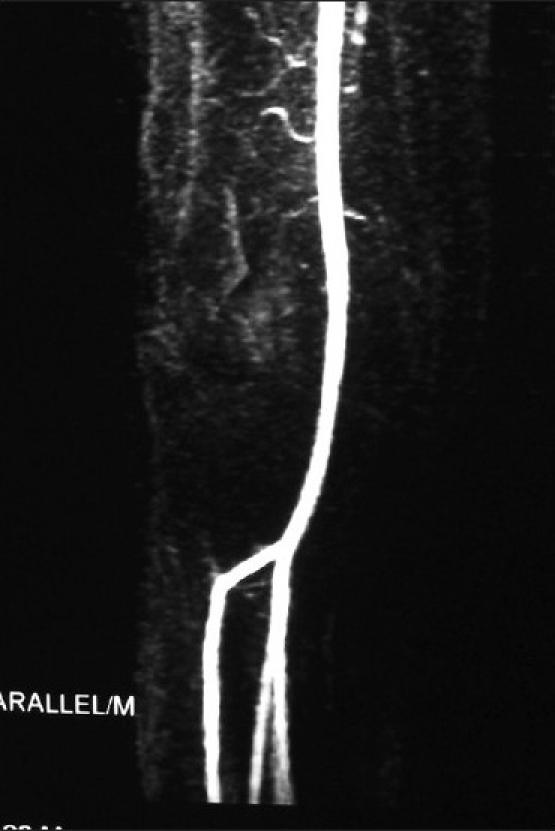

An anterior tibial artery pseudoaneurysm is a rare and unexpected complication of Steinmann pin insertion. We describe the case of an 18-year-old boy, who sustained such an injury to the anterior tibial artery during this procedure. Diagnosis was confirmed on a magnetic resonance (MR) angiogram. Aneurysmal sac excision with lateral repair of the vessel wall was performed. Postoperatively, a good flow was documented on a follow-up MR angiogram. This case highlights a major and unexpected complication of a so-called minor procedure. Too posterior a pin placement in the proximal tibia should be avoided to prevent such injuries.

胫前动脉假性动脉瘤是斯氏针插入术罕见且意外的并发症。我们报告一例18岁男孩在此手术过程中胫前动脉遭受此类损伤的病例。磁共振血管造影证实了诊断。进行了动脉瘤囊切除及血管壁外侧修复。术后,随访磁共振血管造影显示血流良好。该病例凸显了一项所谓小手术的重大意外并发症。应避免在胫骨近端针放置位置过于靠后以防止此类损伤。